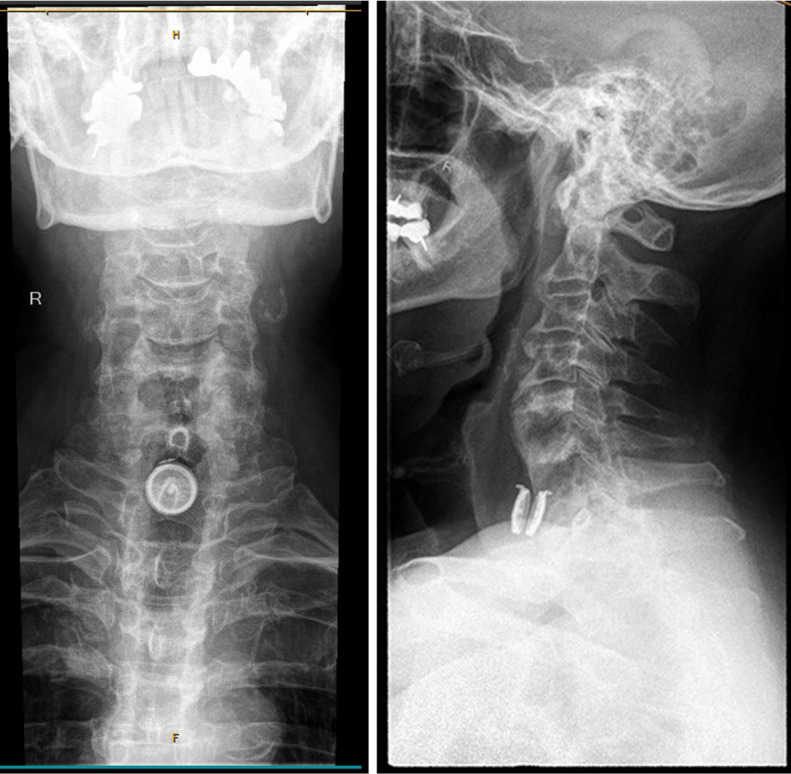

Background: The objective of this report is to present a case of two cervical spine artificial discs (Bryan Cervical Disk) that completely disappeared within 6 months as a result of a high-energy trauma more than 10 years after the initial surgery. Implant dislocation is a known complication in artificial cervical disc replacement. However, this report presents the case of an exceptional migration path with esophageal ingrowth and rectal excretion, not only for one artificial disc but for two at different times It highlights the need for long-term follow-up examinations after artificial cervical disc arthroplasty (ACDA).

Case description: The patient was seen in a Swiss outpatient spine center. He presented with a history of chronic laryngitis, which led to multiple ear, nose, and throat (ENT) diagnostic examinations without any cause being found. Migration of two cervical artificial discs was discovered incidentally in a cervical spine magnet resonance imaging (MRI), which was performed due to chronic myofascial pain in the lower extremities. The MRI showed anterior/retropharyngeal migration of one cervical disc. The second one could not be seen on the whole spine MRI. The complete patient history and radiographic findings were collected and reviewed. In addition, a whole-body computer tomography (CT) scan was done, and the patient was sent to an ENT center to rule out esophagus perforation and to verify the location of the two BRYAN © Cervical Disc.